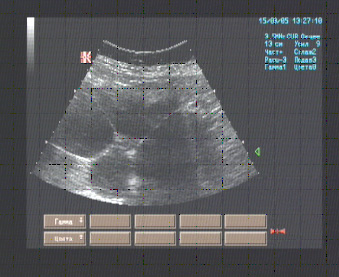

Правая половина живота от правой доли печени до гребня подвздошной кости занята многокамерным жидкостным образованием размерами до 220 х 130 мм. с гомогенным содержимым без отражений. Ограниченное неровными гиперэхогенными стенками толщиной 3-4 мм.

Собственно ткань почки не идентифицируется.

Эхографические признаки кистозного перерождения правой почки, хронического калькулёзного холецистита.